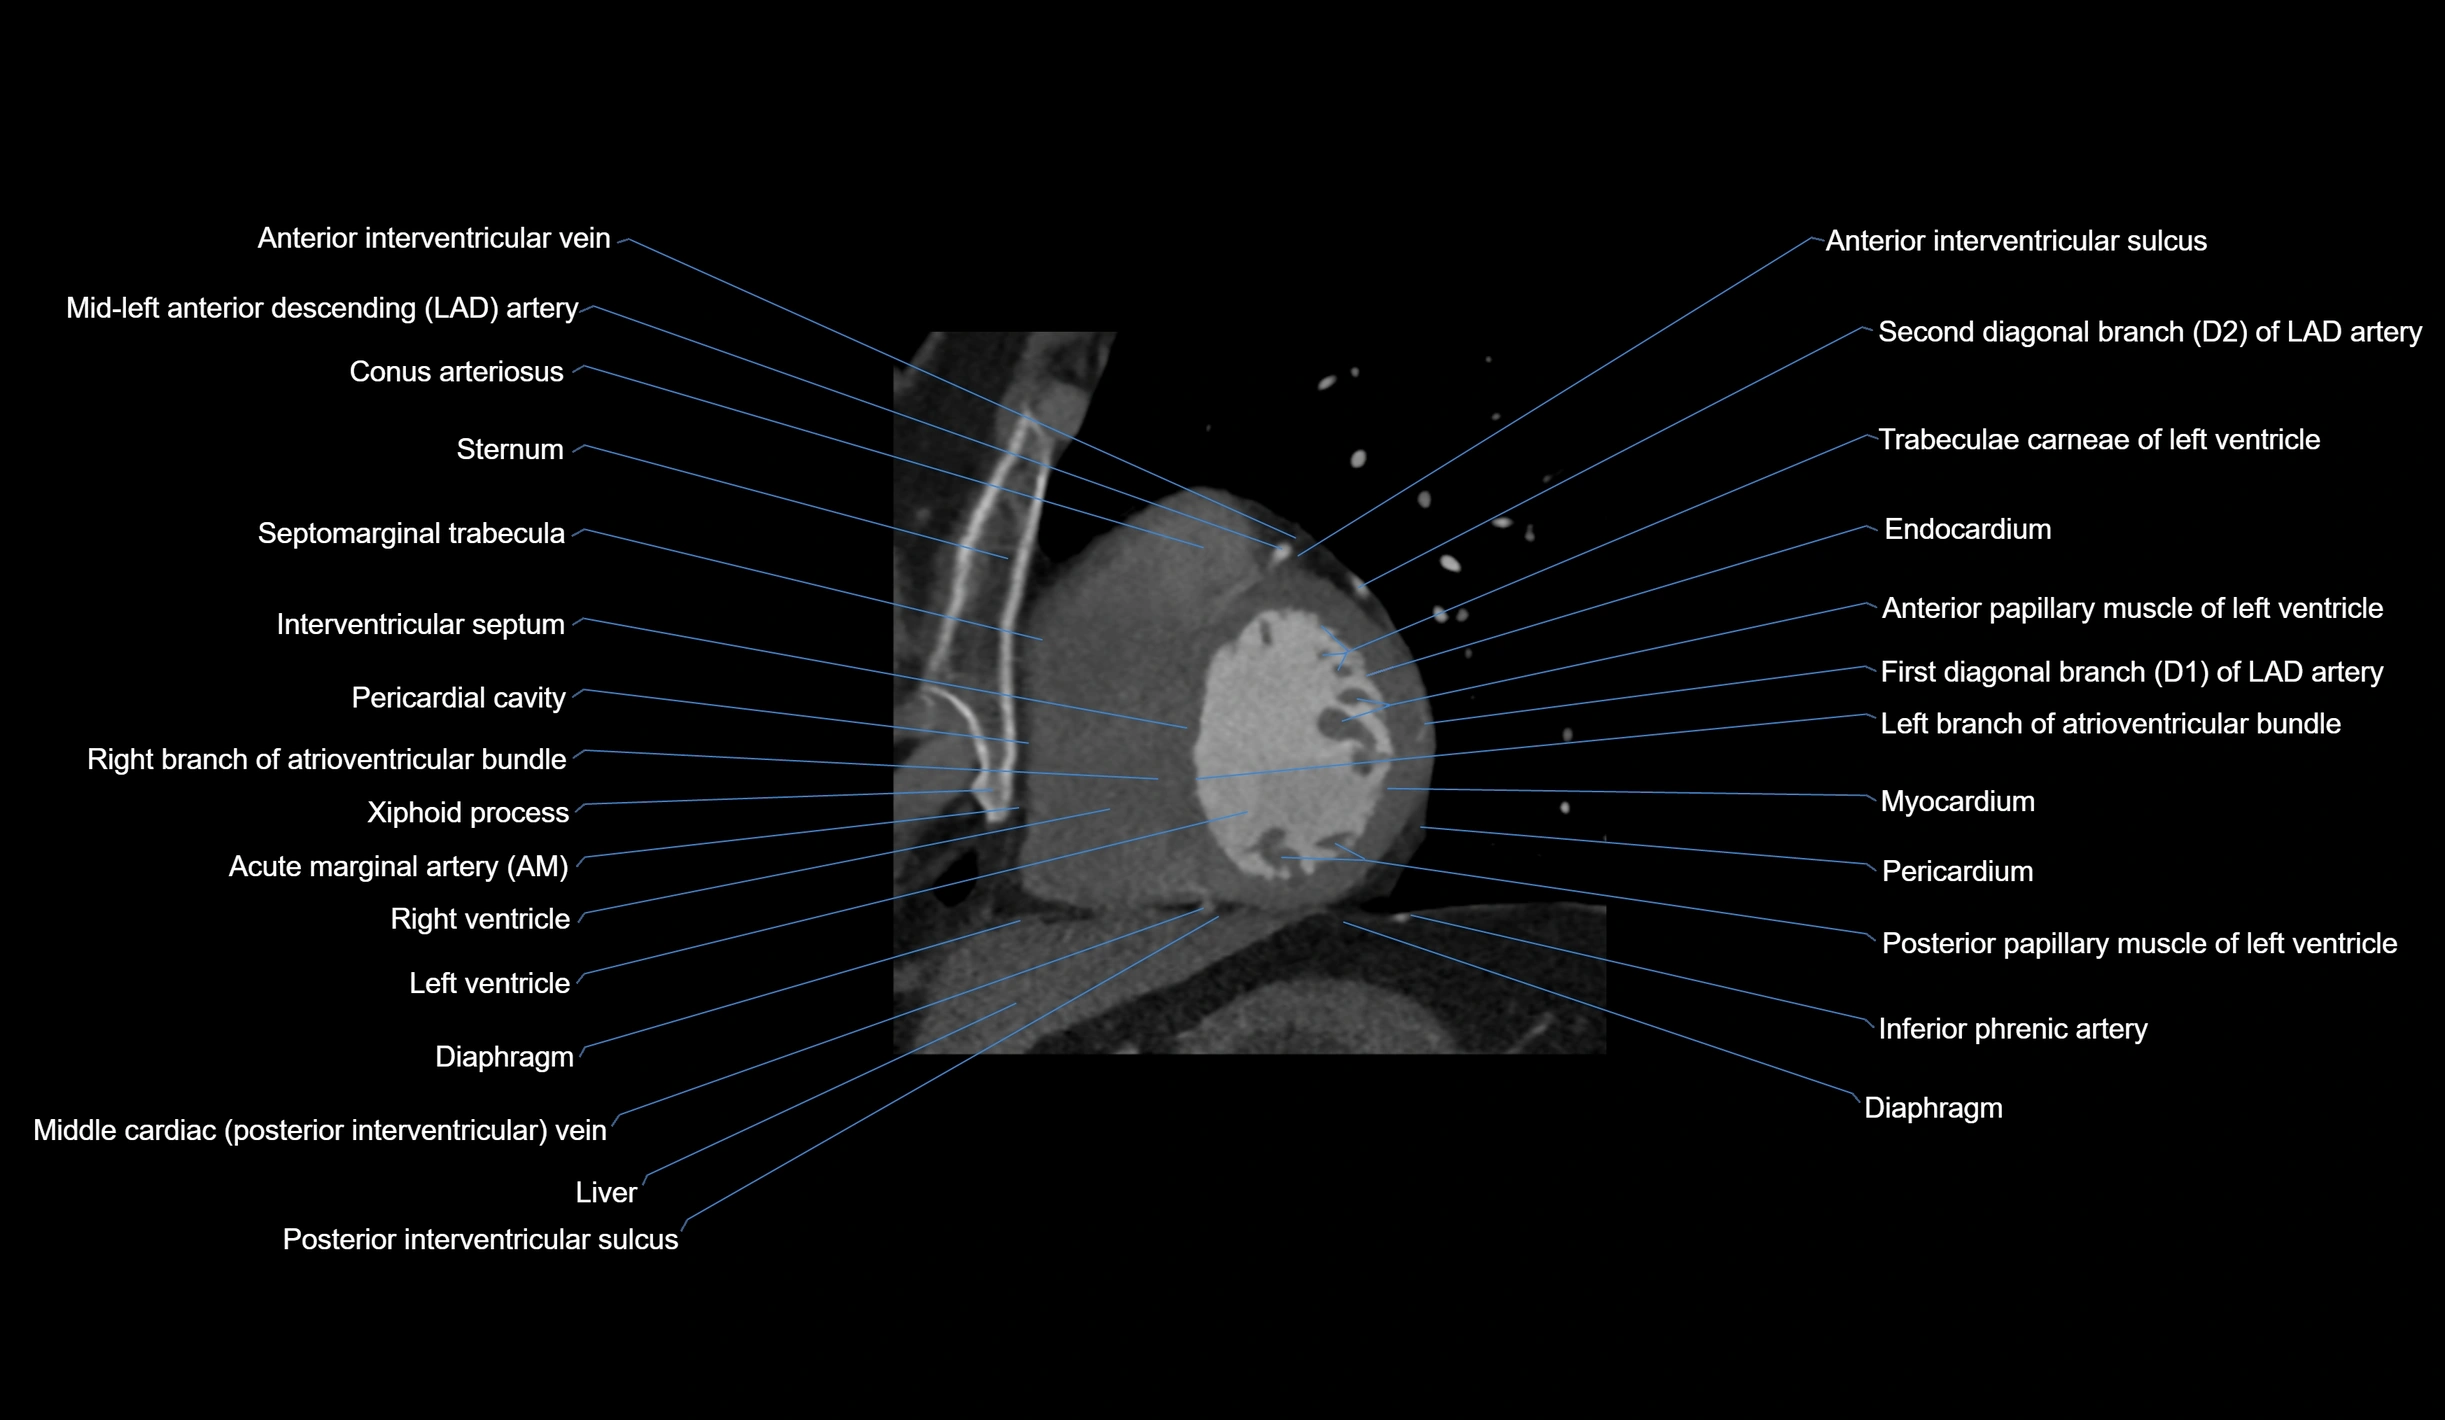

CT images